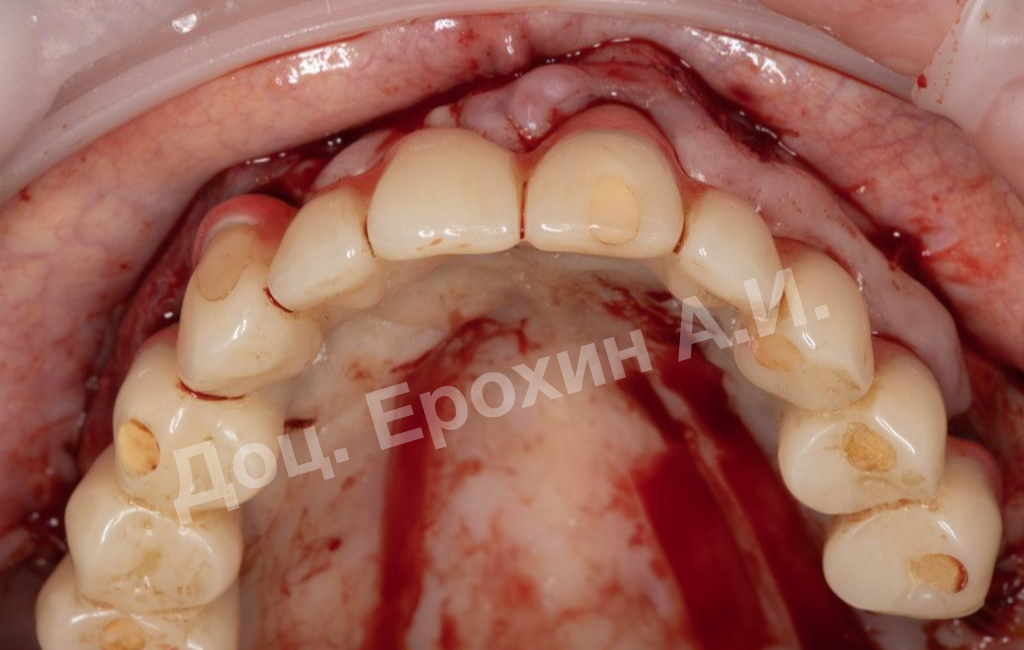

Более 10 лет назад пациентке была проведена тотальная имплантация с полным протезированием. В области имплантатов 22–24 была проведена пересадка эпителиального трансплантата с целью создания зоны кератизированной прикрепленной десны. После проведения данной операции пациентка по личным причинам не захотела заниматься мягкими тканями и пропала на 10 лет.

В результате, спустя 10 лет мы видим, что единственная часть десны в области имплантации, не затронутая рецессиями, — это зона, где была проведена трансплантация десневого фрагмента. С целью стабилизации имеющихся имплантатов на повторном приеме была проведена вестибулопластика по Кларку с фиксацией мягкотканных мукотомов, фрагментов эпителия с неба, зафиксированных швами.